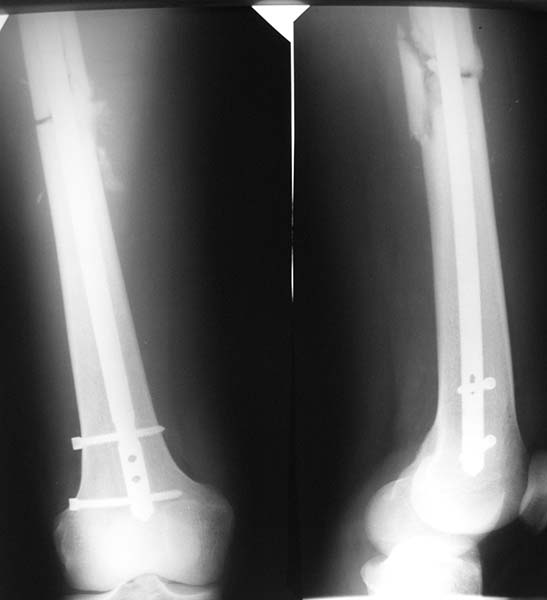

Доброго времени суток, уважаемые коллеги! Наверняка у кого-нибудь есть опыт удаления сильно погнувшегося блокирующего винта из круглого отверстия штифта.Может быть вы применяли какие-то приемы или хитрости?Если не трудно, поделитесь.Спасибо!

Снимок покажите. Какой срок после остеосинтеза?

Год. Собираемся рассверлить и реостеосинтезировать.

Срок слишком большой. И несращение и так обусловлено нестабильностью, судя по картине. И усугубление нестабильности может завесить проблему на неопределенный срок. Или до перелома собственно гвоздя.

Может быть - если месяцев 10 назад. А так - вот она потом произошла, "самодинамизация". Статический винт давно сломался, место несращения просело чуть не на сантиметр, динамичесий винт проехал до верхнего края отверстия. Так что можно бы растянуть псевдартроз, и запереть статически, сохранив напряжение на дистракцию.

Хотели установить максимально толстый штифт и блокировать динамически. Послеоперационные снимки прилагаются.